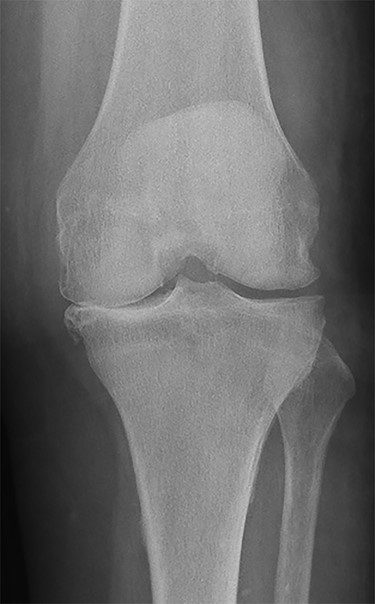

Conventional radiographs in an anteroposterior and lateral view showed advanced osteoarthritis (Kellgren stage III) accentuated medially and patellofemoral (Figs 1 and 2). An additional magnetic resonance imaging (MRI) was performed, which confirmed the medial accentuated osteoarthritis, it revealed some minor meniscal tears, some signs of general synovitis and joint effusion (Figs 3 and 4).